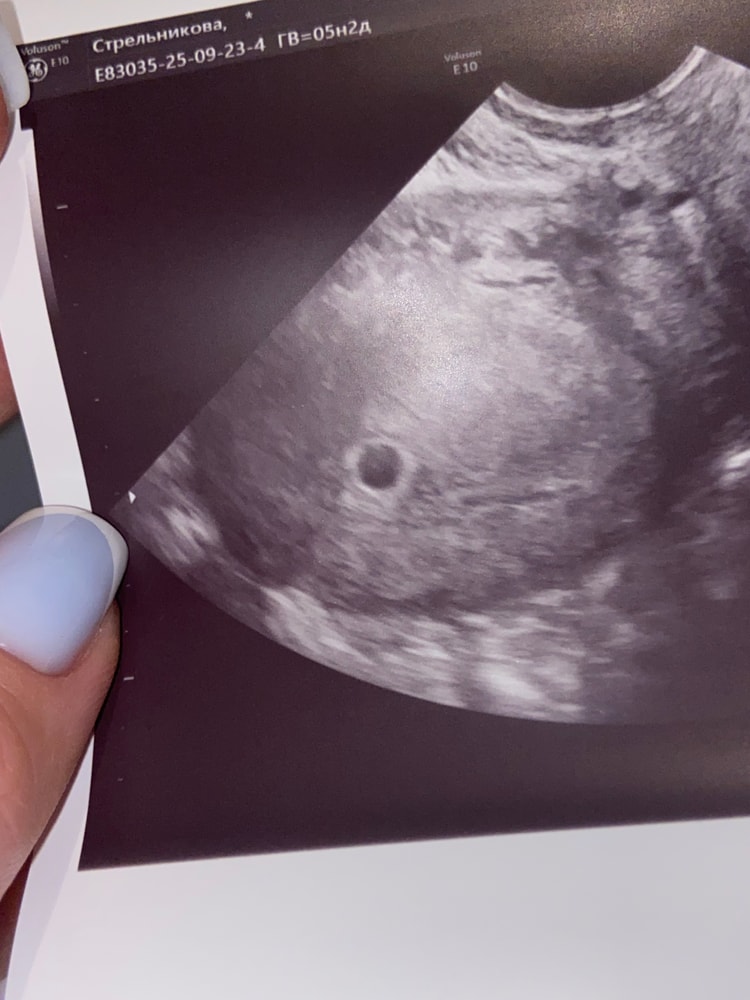

Вчера узи показало девочку 15.5 недель